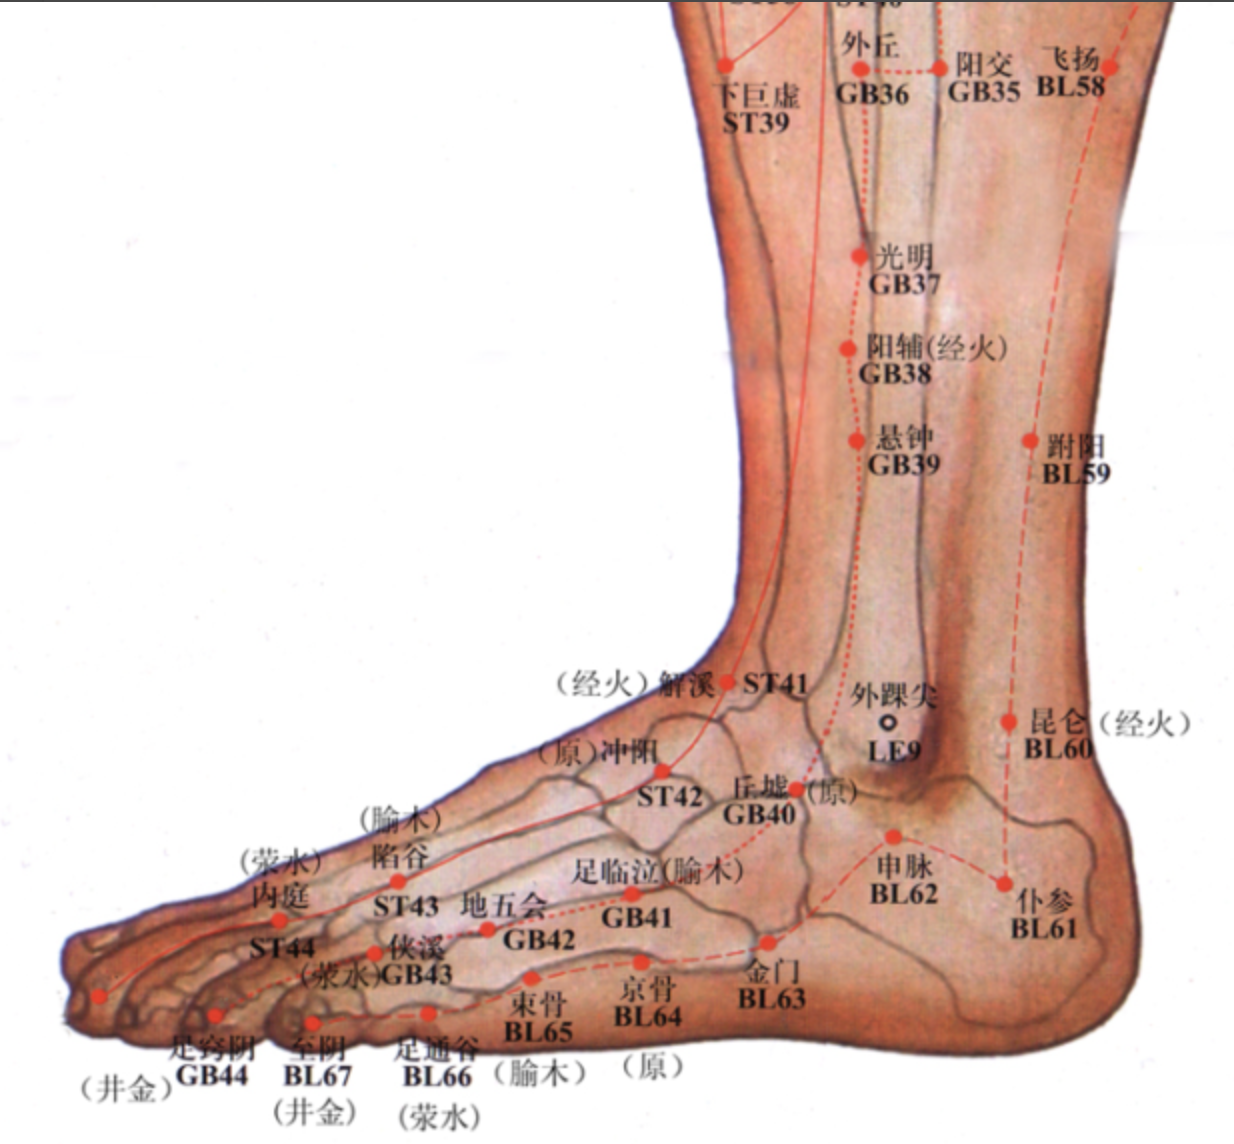

【(七)足太阳膀胱经(图 10-25-1)】

昆仑

至阴

【(十一)足少阳胆经(图 10-29-1)】

阳陵泉

光明